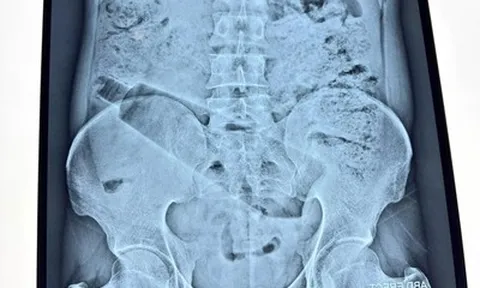

Bệnh viện cũng đẩy mạnh ứng dụng công nghệ thông tin trong toàn bộ quy trình khám chữa bệnh. Hệ thống lấy số tự động, thanh toán điện tử và trả kết quả xét nghiệm trên phần mềm giúp người bệnh không phải di chuyển nhiều lần giữa các khu vực.

Sau khi xét nghiệm hoặc chụp chiếu, kết quả được cập nhật trực tiếp lên hệ thống, bác sĩ có thể xem ngay trên máy tính và gọi bệnh nhân vào tư vấn, thay vì phải chờ in kết quả giấy như trước.

Ông Nguyễn Trường Nam, Phó Giám đốc Trung tâm Thông tin Y tế Quốc gia, Bộ Y tế cho biết, các đơn vị trong ngành y tế đang đẩy mạnh chuyển đổi số. Nhiều bệnh viện áp dụng y tế thông minh trong quản trị như đặt lịch khám qua điện thoại, lấy số tự động, triển khai thanh toán không dùng tiền mặt, xây dựng hệ thống bệnh án điện tử, hồ sơ sức khỏe điện tử, lưu trữ và truyền tải hình ảnh (PACS) thay cho in phim.